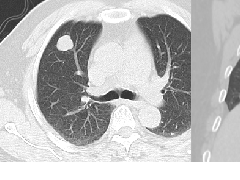

肺段与肺内管道应用解剖  肺转移瘤的十种不典型CT表现

肺转移瘤的十种不典型CT表现  肺内淋巴结的CT表现特点及与病理对照